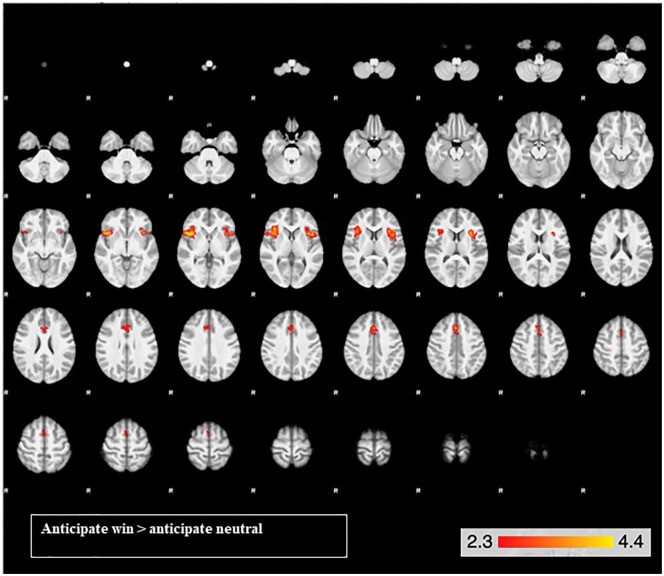

Effects of task (Table 2; Figures 2 and 3)

For the reward anticipation contrast, there was activation in three clusters, with peak activations in the insula bilaterally and the right paracingulate gyrus (Table 2). The right and left insula clusters extended into the right and left frontal operculum cortex, inferior frontal gyrus and orbitofrontal cortex. The paracingulate gyrus extended into the anterior cingulate gyrus, supplementary motor cortex and superior frontal gyrus (Figure 2).

Table 2.: Activations for the reward anticipation (anticipate-win>anticipate-neutral) and reward feedback (feedback-win-hit>feedback-neutral-hit) contrast across both drug conditions. The table shows, for each cluster: the brain regions; cluster-corrected p values for each cluster; k (the size of each cluster, in terms of number of voxels); z value for the peak in the cluster; and the co-ordinates for the centre of gravity (COG) in Montreal Neurological Institute (MNI) space.

| Right insula | 0.003 | 801 | 4.42 | 41.1 | 18.2 | 2.4 |

| Left insula | 0.008 | 702 | 3.89 | –38 | 14.5 | 15.2 |

| Paracingulate gyrus | 0.013 | 642 | 3.65 | 1.9 | 19.0 | 40.7 |